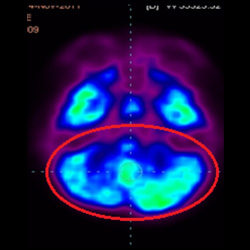

干細(xì)胞治療腦癱后改善的客觀放射學(xué)證據(jù)

細(xì)胞治療前 PET CT 掃描顯示神經(jīng)組織中的藍(lán)/黑色區(qū)域,表明腦癱引起的大腦損傷。

這證明細(xì)胞療法是治療腦癱兒童安全有效的方法。細(xì)胞療法可以更新大腦損傷的核心,并且可以通過 PET CT 掃描來監(jiān)測大腦的改善情況。這些細(xì)胞療法與標(biāo)準(zhǔn)治療一起促進(jìn)腦癱兒童的生長和改善。